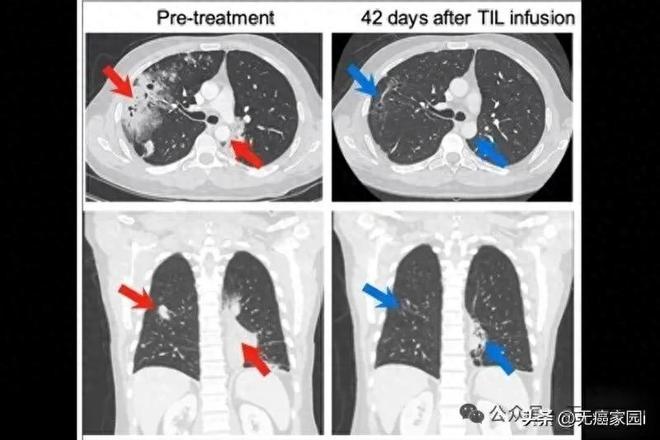

上图为一位在MSK接受治疗的肺癌患者的CT扫描,从两个不同的角度拍摄。这些图像分别展示了患者接受TIL治疗前和治疗6周后的胸部情况。左侧的治疗前图像显示胸腔内有大面积的癌症区域(红色箭头所示)。右侧的治疗后图像显示癌症区域显著缩小(蓝色箭头所示)。CT扫描显示,TIL输注后12周,根据RECIST v1.1标准,部分缓解率为81%。